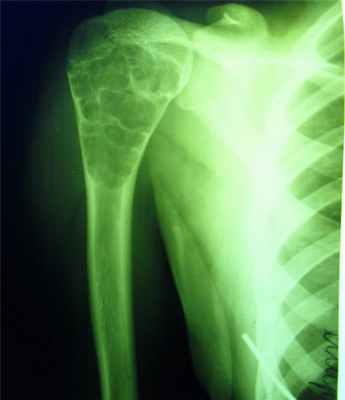

Гиперостоз — это остеосклероз плюс увеличение объема, утолщение кости. Такое состояние прямо противоположно атрофии. Гиперостоз — это утолщение кости за счет периостального костеобразования, он наблюдается при хронических остеомиелитах, сифилисе, болезни Педжета.

Различают гиперостоз одной или нескольких костей, например, при сифилисе, болезни Педжета и гиперостоз генерализованный, когда наблюдается поражение всех длинных костей скелета при хронических заболеваниях легких: хроническом абсцессе, длительно текущих хронических пневмониях, раке легких.

Различают также гормональные гиперостозы, к примеру, увеличение объема костей при акромегалии.

Эностозом называют увеличение массы кости за счет склероза эндооста.